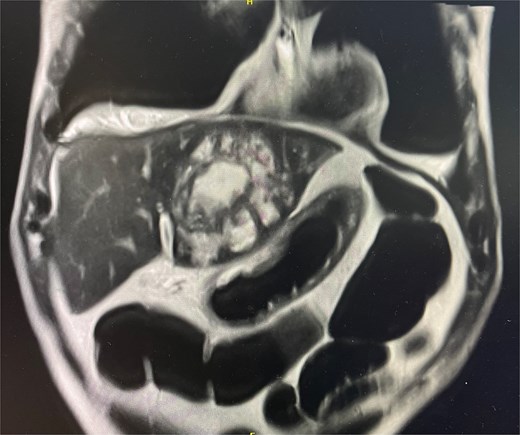

Cross-sectional imaging with ultrasound, computed tomography (CT) (Fig. 1), and magnetic resonance imaging (MRI) (Fig. 2) showed a rapidly-growing large, complex lesion measuring ~55 × 39 × 43 mm in the left hepatic lobe, with features suggestive of an evolving abscess but no drainable collection. Empiric IV piperacillin-tazobactam was commenced.

MRI liver in coronal slice. Hepatic abscess seen in left hepatic lobe.